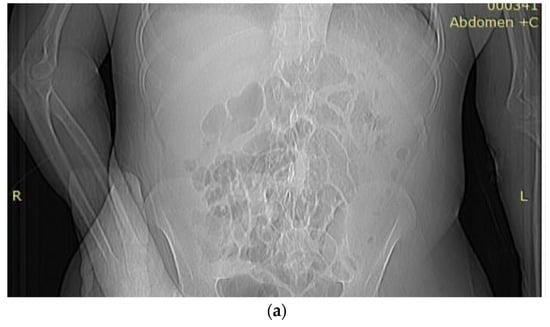

We present the case of a 44-year-old woman from an urban area, known to have liver cirrhosis with hepatitis B virus therapeutically neglected, a duodenal ulcer surgically treated for perforation, and upper digestive hemorrhages in her personal history, requiring blood transfusions. We also note that the patient was in the nephrology records from 2015 with advanced chronic kidney disease (CKD) that required hemodialysis every three days. She presented by herself to the emergency room for acute ischemia phenomena with forearm and right compartment syndrome (Figure 1a), requiring hospitalization for surgical decompression in the Plastic Surgery Clinic.

Figure 1.

(a) Acute ischemia phenomena and forearm and right-hand compartment syndrome. (b) Bilateral hand onycholysis.